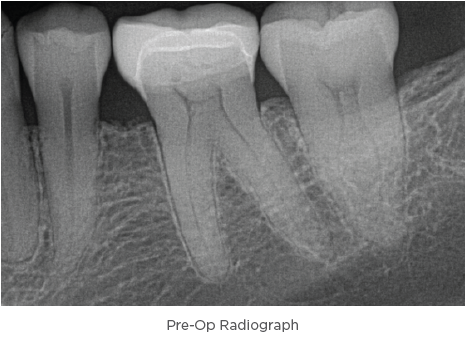

4. The canals were dried before placing ZenSeal™ Bioceramic

Sealer (Figure 3).

5. The canals were obturated using SimpliCore™ for Zen-

Flex™ ONE Primary (Figures 2 and 3).